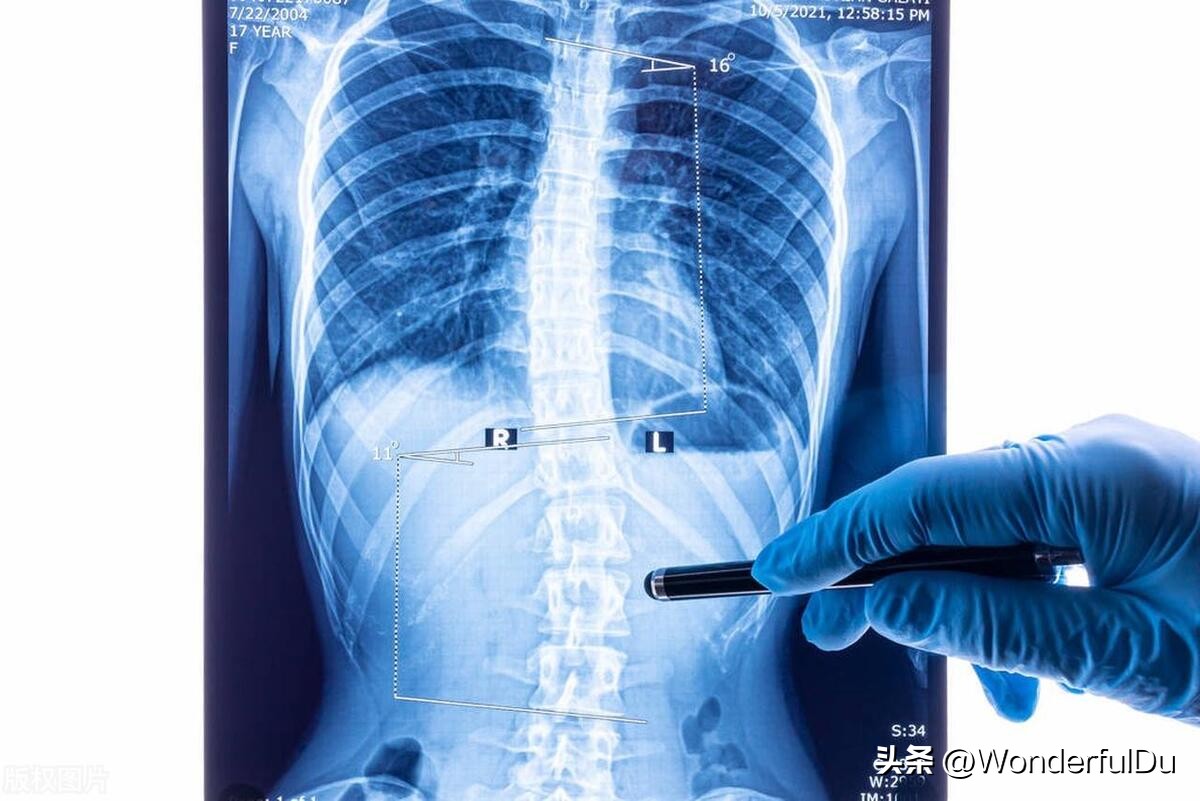

2、X光片前后对比检查

2022-10-6龙脊康支具下全脊柱 DR 阅片提示:胸椎以T8为中心向右侧凸, Cobb角≈19° ;腰椎以L2为中心向左侧凸, Cobb角≈18° 。

2023-04-08龙脊康脱支具全脊柱片:胸椎以T8为中心向右侧凸, Cobb角≈12° ;腰椎以L2为中心向左侧凸, Cobb 角≈17° 。

X光片对比图

从X光片上的话,胸椎从19°减至12°,腰椎从18°减至17°,虽然说度数减的不是很多,但是从片子上看, 中线回正很多 ,整个人是处于中立位的,基本处于一个相对稳定的状态。